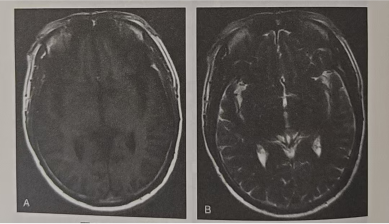

急性期(<1周):血栓内红细胞处于脱氧血红蛋白状态,T1WI呈等或高信号(图2A),T2WI呈低信号(图2B),通常可见窦腔扩大,偶尔可见血管内低信号和静脉扩张征象;DWI及ADC影像显示血栓所在区域可能表现为弥散受限,但此时血栓在T2WI呈低信号改变,常被误认为正常流空效应而漏诊。

图片

图2.硬脑膜静脉窦血栓急性期影像学表现A.T1WI示上矢状窦内为高信号;B.T2WI显示上述区域为低信号